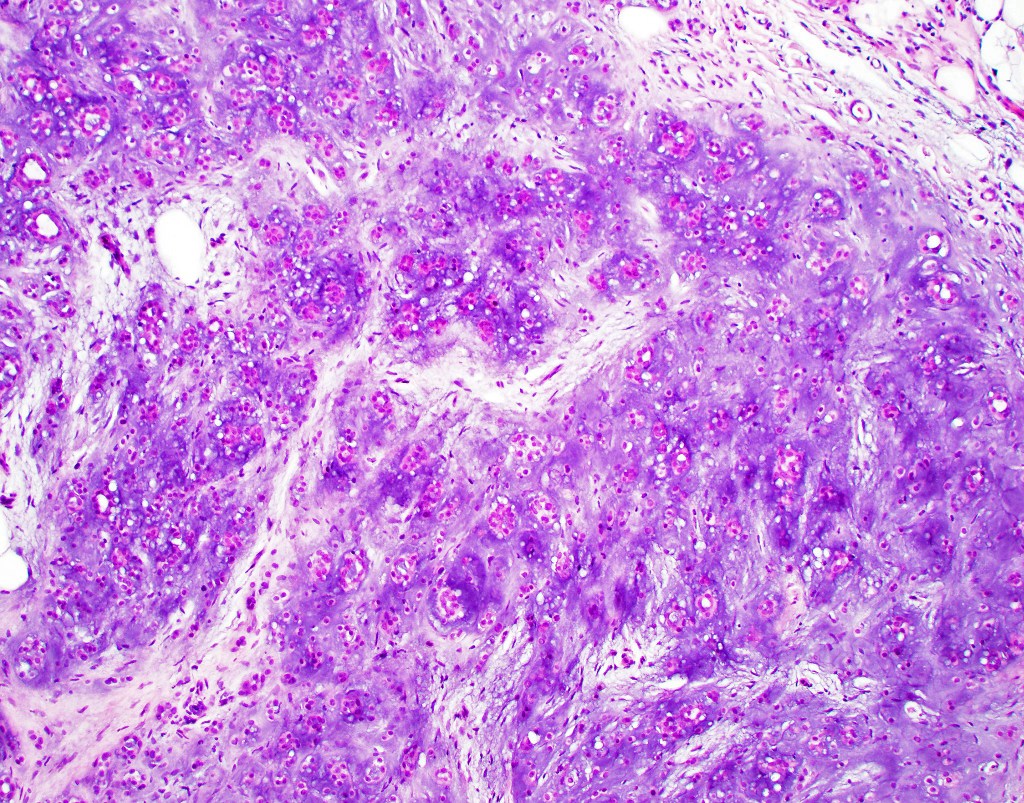

•Infiltrative growth pattern

•Nuclear pleomorphism, prominent nucleoli

•Marked mitotic activity

•Abnormal mitoses